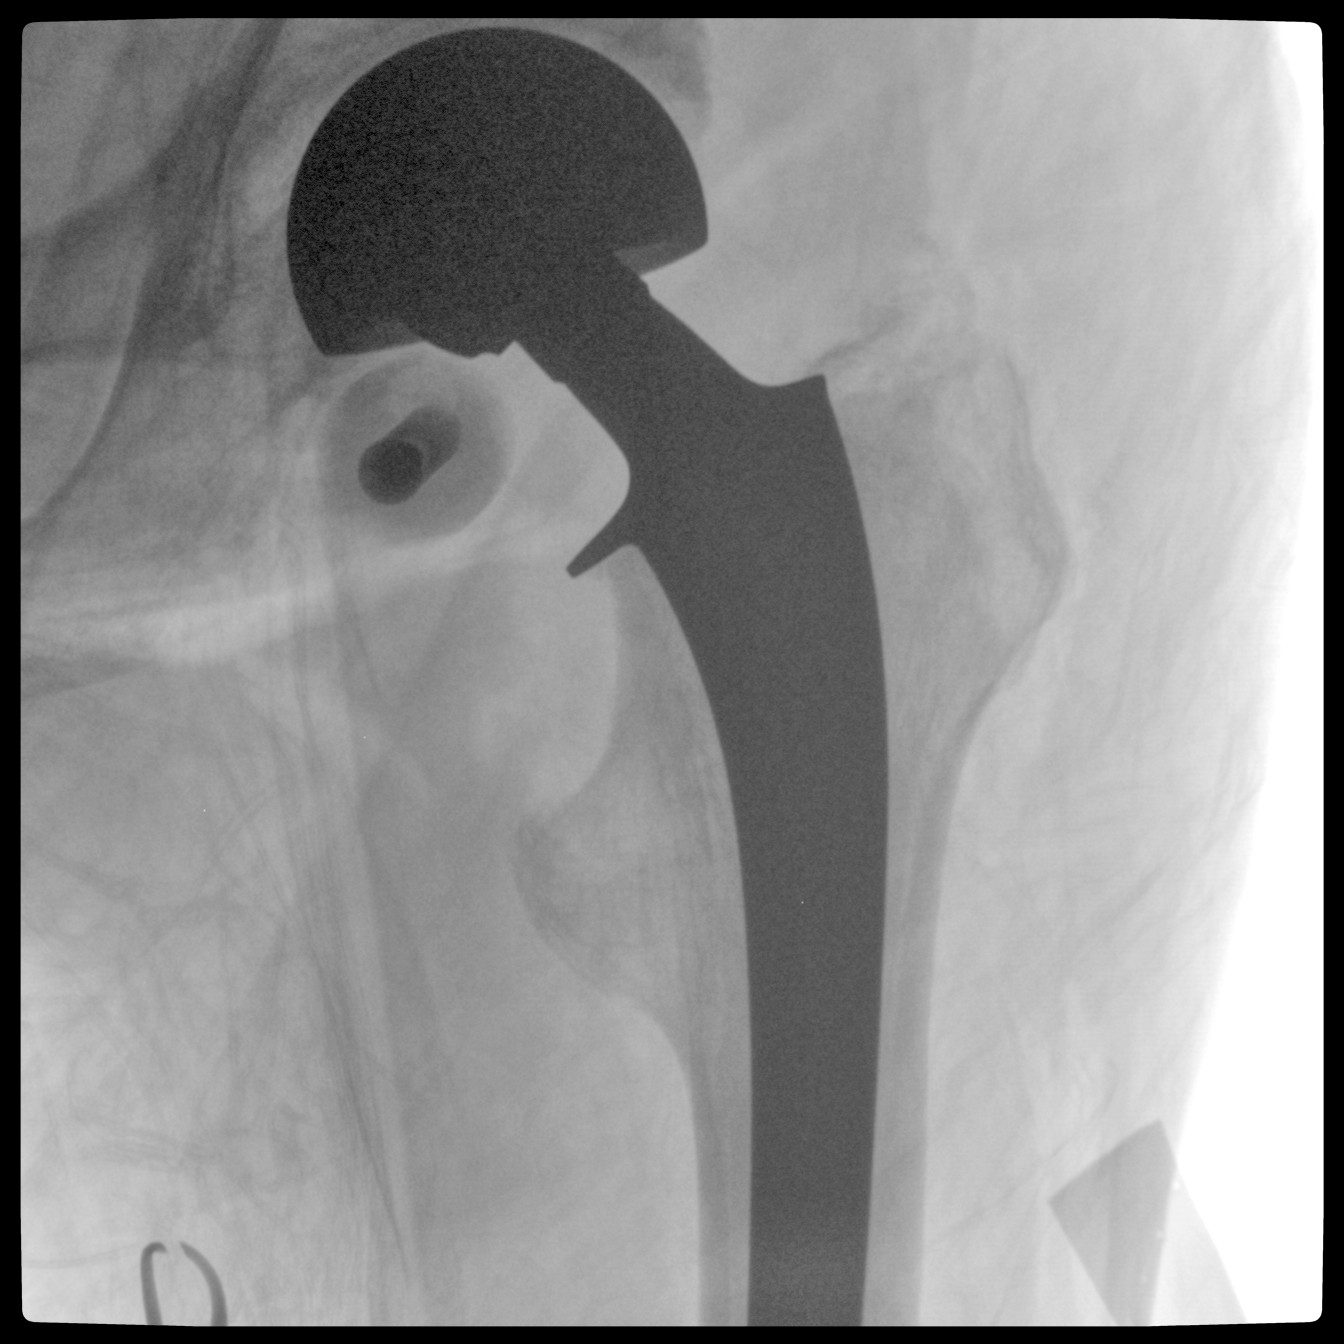

Clinical picture

臨床圖片